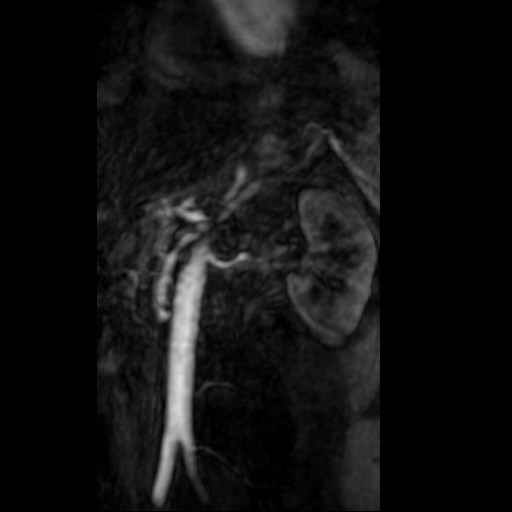

Angio abdominaal